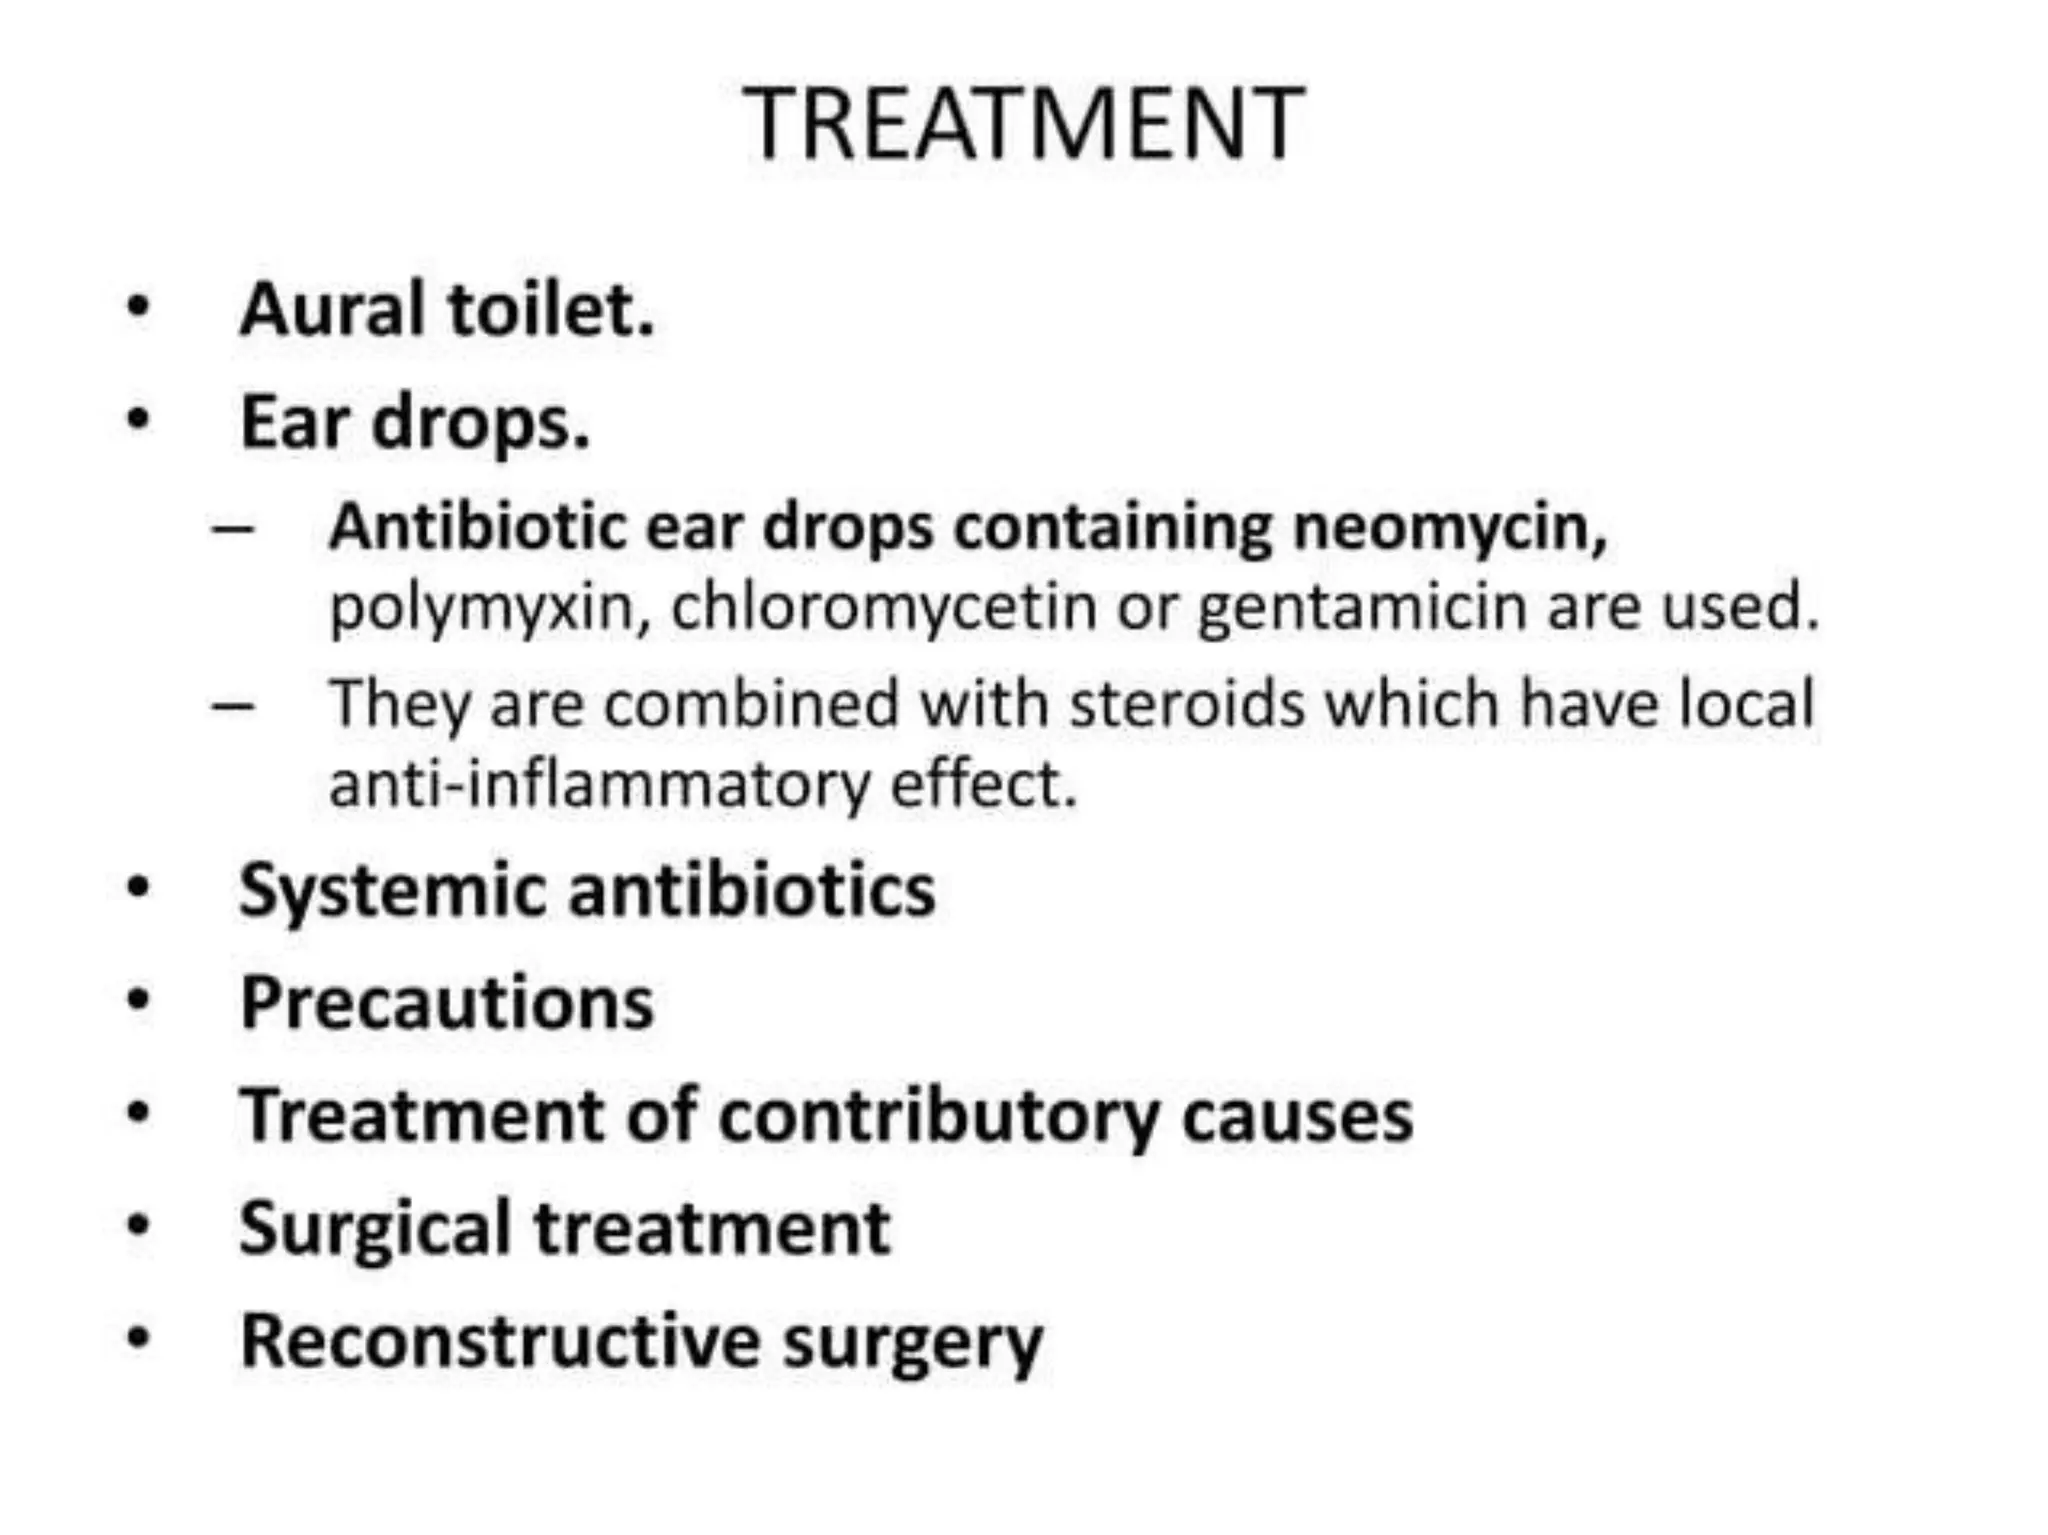

Chronic otitis media is a chronic inflammation of the middle ear and mastoid cavity that presents with recurrent ear discharge through a perforated eardrum. It has several subtypes depending on the state of the eardrum perforation and epithelium. It can be caused by prior acute otitis media, genetics, environment, eustachian tube issues, gastroesophageal reflux disease, craniofacial abnormalities, or immune deficiency.